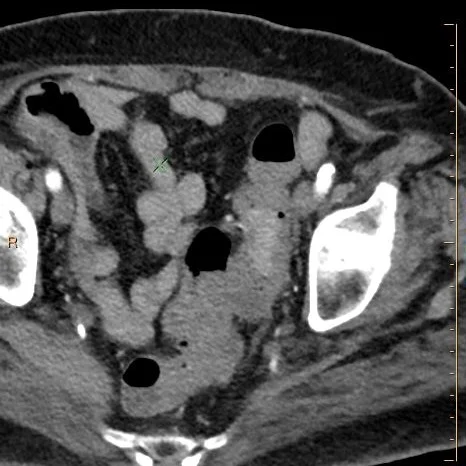

68 year old female gets a screening colonoscopy. A sigmoid colon mass is discovered and biopsied. Patient is then sent to CT scan for staging. On conventional images it is very difficult to appreciate the sigmoid mass. Is it important to find the mass, or just look for metastasis?

Conventional CT: Can you really see the mass?